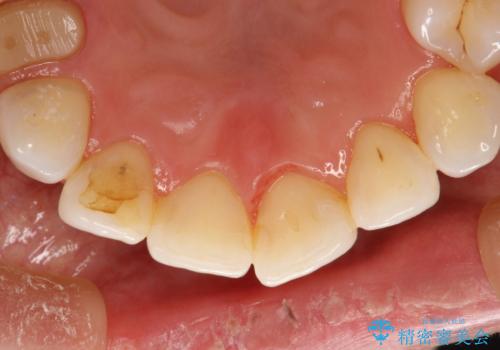

PMTC30分コース(保険外治療)を行いました。かなり久しぶりの歯科医院へ来院とのことで、プラーク(歯垢)・歯石・ステイン(着色)が付着していました。汚れを除去し、本来のご自身の歯質にすることでなにか異常があった際に発見しやすくなります。

また、今回はクリーニング後に、何か所か虫歯や治療途中のままの部分が発見されました。今後は定期的なメンテナンス・クリーニングと併用しながら虫歯の治療を行っていく予定です。